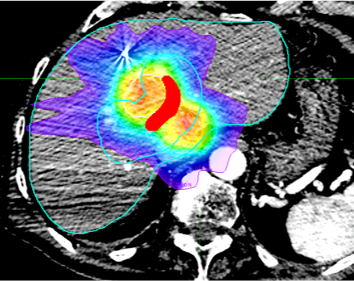

AI for radiotherapy planning

Radiation dose kills both cancer and healthy tissue cells. The modern radiotherapy equipment allows high personalization of dose delivery, which however does not allow complete sparing of healthy organs surrounding the tumor and up to 27% of treatment result in radiation-induced toxicities. It is very challenging to predict if a radiotherapy will result in toxicities. This research project develops machine learning solutions for the analysis of pre-radiotherapy medical images, spatial relationships among tumors and surrounding organs-at-risk, prescribed dose plans, concurrent-to-radiotherapy treatments and patient’s profile for the prediction of radiotherapy outcomes.